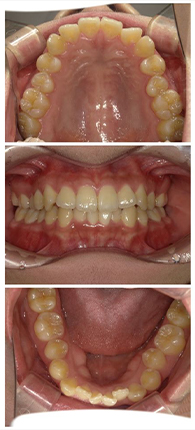

症例紹介

症例1

八重歯きれいにして前歯のガタつきを治したいとご来院された女性の症例です。

抜歯をして、1年半で完了しました。

約1年半後

ホワイトニング併用

| 治療費用 | 矯正検査代 33,000円、基本治療費 990,000円、調整料 5,500円×18回、 保定装置 55,000円、ホワイトニング剤 6,600円 |

| 治療のリスクについて | ホワイトニングでは歯がしみることがありますが、当院では知覚過敏予防の歯磨剤をお渡しし、症状の軽減に努めています。また、矯正治療においては歯肉退縮のリスクがありますが、丁寧な歯磨き指導を行うことで予防に取り組んでいます。 |

症例2

前歯の歯並びをきれいに整えたいとご来院された20代女性の症例です。18枚のインビザラインを用いて上下の歯列を拡大し、骨格に問題のないⅠ級叢生のケースに対応しました。

約10か月後

| 治療費用 | 矯正検査代 33,000円、基本治療費 660,000円、調整料 5,500円×10回、 保定装置 55,000円、ホワイトニング剤 6,600円 |